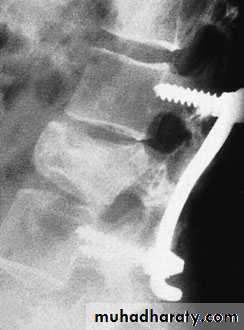

Lumbar Spine X Ray

Lateral radiograph